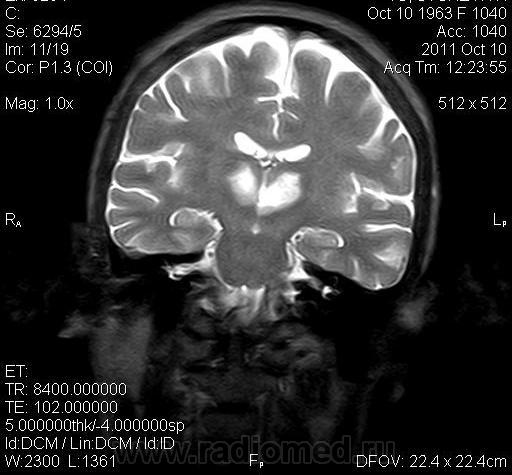

женщина 1963 года рождения. давность заболевания 10 дней.

Билатеральный таламический инфаркт. Либо венозный, либо вследствие закупорки одной из ветвей задней мозговой артерии - ЗМА (вариан развития ЗМА). Но не средней мозговой артерии (СМА). Мне представляеться, что здесь второе... За венозный инфаркт данных не вижу.

Может не как следствие закупорки сосуда, а гемодинамический инфаркт в ВББ (таламо-субталомических ветвей ЗМА)?

MELAS? Чем черт не шутит?

MELAS- по лаколизации очень похоже, но пока нет достоверных данных на него указывающих

Я неприклонен... Инфаркт ЗМА (вероятно, варианта развития левой ЗМА - эмболии, мойа-мойа..).